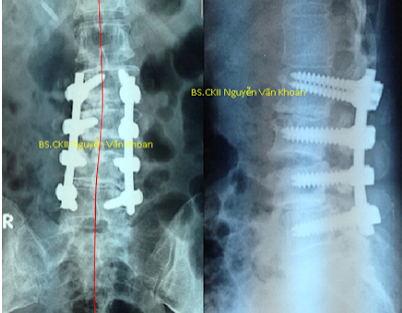

Phẫu thuật gồm việc nắn chỉnh cột sống về càng gần như bình thường càng tốt, bằng dụng cụ ốc chân cung và thanh nối dọc phía sau, và hàn xương để cố định cột sống (thường dùng xương ghép lấy từ mào chậu của chính bệnh nhân). Dụng cụ thường để luôn trong cơ thể không cần mổ lấy ra. Sự phục hồi sau mổ cũng khác nhau tùy từng người. Sau mổ bệnh nhân được truyền máu (nếu mất máu nhiều), truyền dịch, kháng sinh, thuốc giảm đau. Bệnh nhân được khuyến cáo tập ngồi và đi lại càng sớm càng tốt nếu có thể với sự trợ giúp của chuyên viên vật lý trị liệu, để giúp phục hồi sức mạnh khối cơ.